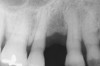

Figure 5  Recurrent decay of teeth Nos. 11 and 12. Note the proximity of the decay on both teeth to the osseous crest.

Figure 5

In treatment planning, the decay rate of the patient’s teeth, including the endodontic status of the individual tooth, becomes an important factor when considering long-term outcomes. In the pictured case (Figure 5), tooth No. 11, which previously had been treated endodontically, had recurrent decay and tooth No. 12 had advanced decay with endodontic involvement. In less than 30 days, recurrent decay that reaches the endodontic fill through a leaky restoration (temporary or not), ill-fitting crowns, or broken fillings can re-infect the entire length of the root canal system in a previously endodontically treated tooth.22 Therefore, saving a previously endodontically treated tooth, as in this case, may involve endodontic re-treatment, which can be a deciding factor for tooth preservation.

In addition, xerostomia becomes more likely with advanced patient age and/or the use of certain medications.23 This problem can lead to a higher decay rate, which has implications for a situation similar to the above case. In this case, in which tooth No. 12 would need endodontic treatment, surgical crown lengthening, a post, a crown, etc, to save it, the alternative of extraction and implant placement should be considered. The implant would not be susceptible to future decay, root fracture, or endodontic failure. The fee for this treatment also may be comparable to tooth preservation. If the tooth also requires a post, core, or other treatment, then its prognosis24 would be less optimistic than that of a dental implant. Also, if the implant can be placed at the time of extraction, there would be only one surgical visit; whereas, the endodontic and crown-lengthening procedures usually involve many treatment visits.

Bone removal is also a factor. In this example, tooth No. 12 had a short root. Removal of bone to reestablish a 3-mm biologic width as well as about 2 mm of ferrule25 would decrease the long-term prognosis of the tooth, especially because there would be an existing compromise regarding the crown-to-root ratio.26 Osseous recontouring for crown lengthening also may remove bone from the adjacent teeth (in this example, the distal of tooth No. 11).